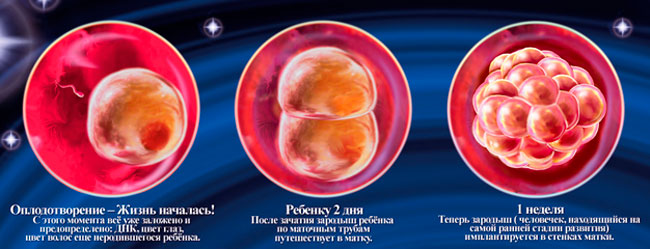

Развитие эмбриона: Что происходит на 3 неделе беременности

Раздел: Фотопанорама